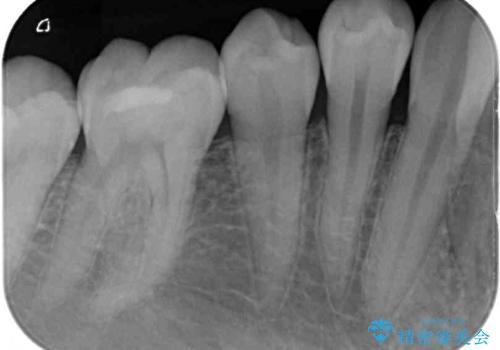

- 右下の奥歯が噛んだ時に痛み、冷たいものがしみることを主訴として来院された患者様です。

精査の結果、歯が欠けていてその下に虫歯が認められました。

また、咬合面(歯の噛む面)に以前治療した樹脂の詰め物があるため、一度外して虫歯を完全に除去し、

精度の高いセラミックインレーにて修復処置することとしました。